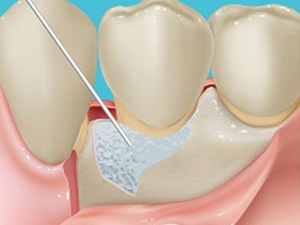

CTG(結合組織移植)保険適応

歯茎が痩せた場合や抜歯後に歯茎が陥没した場合は上顎の口蓋から結合組織を移植します。歯根を覆う歯肉を厚くできるので、ブラッシングがしやすくなります。